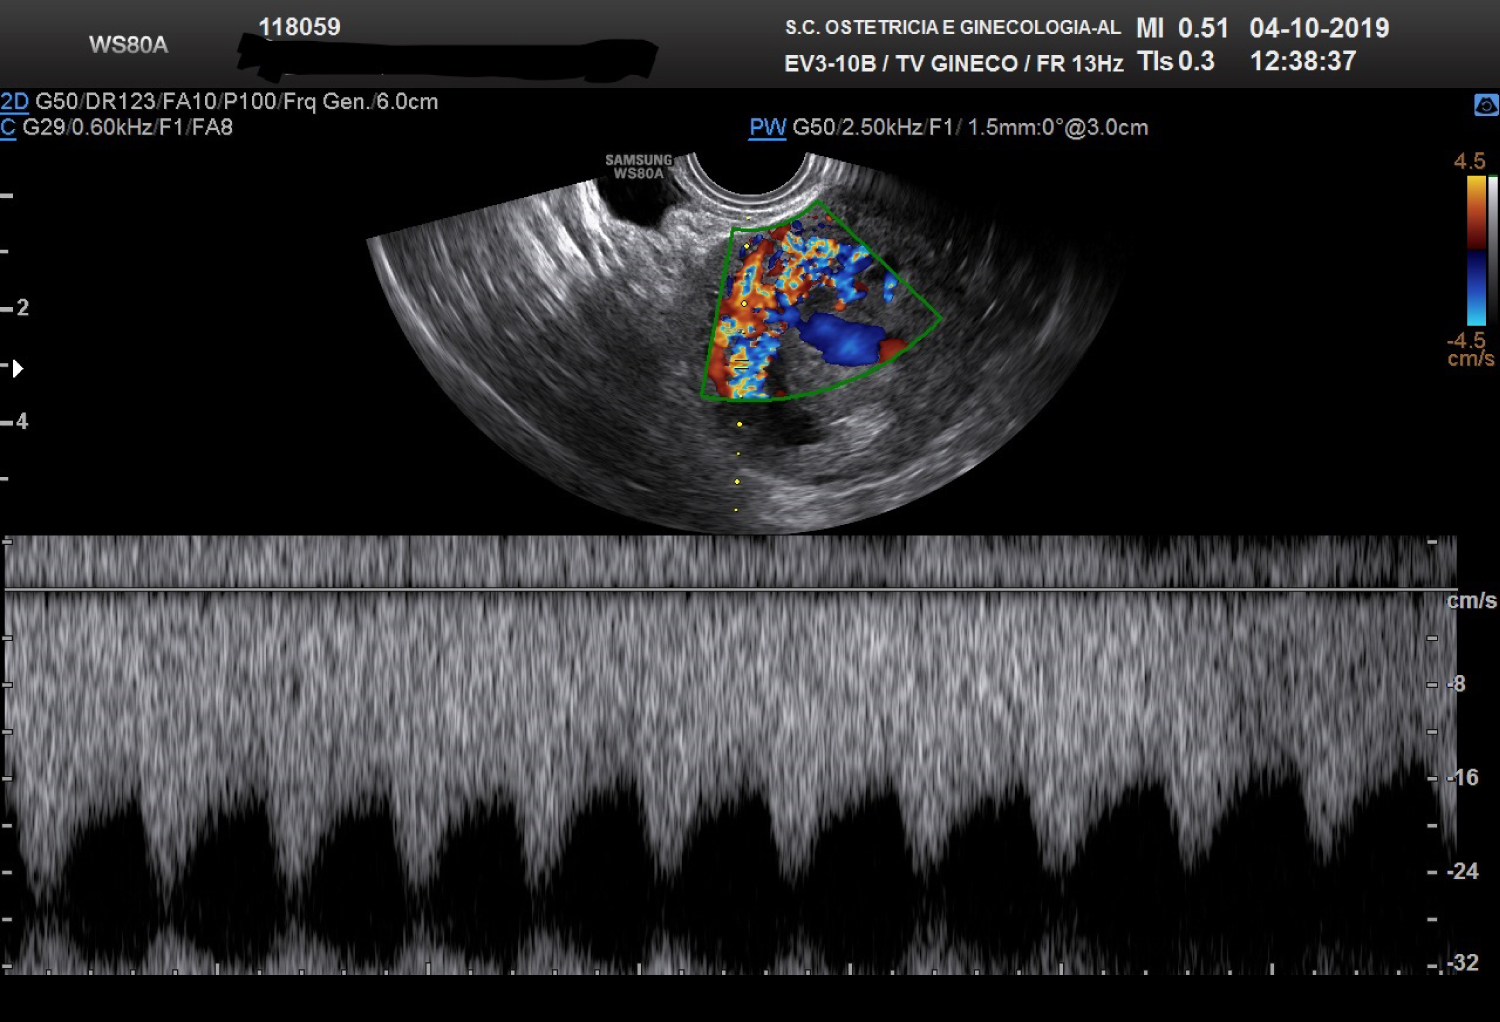

The patient was thereafter managed considering the diagnosis of UAVM. D&C was not performed for two main reasons: High risk of bleeding secondary to the hypervascularization of the uterine formation, high risk of developing further vascular anomalies in the hypothesis the patient were affected by HHT as her mother and her sister. On the 9th October the patient underwent embolization of the right uterine artery since the blood supply was found at angiography coming mainly from that artery (Figure 2). On the same day serum betaHCG were dosed on blood and the levels were undetectable.

Figure 2: Selective uterine angiography before embolization. View Figure 2